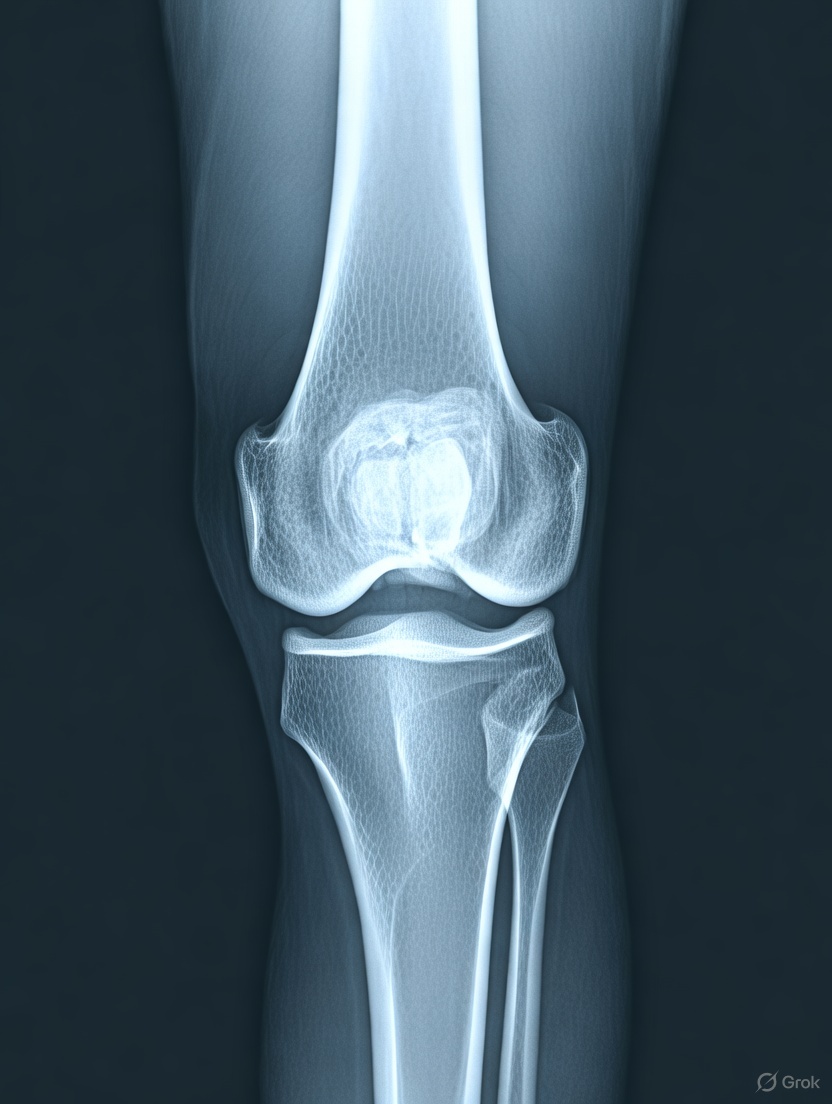

Yapılan son klinik denemelerde osteoartrit yani diz ağrılarını hafifletmede düşük doz radyasyonunun işe yaradığı bulundu. Özellikle kadınlarda belli bir yaştan kemik erimesiyle ortaya çıkan diz ağrılarında düşük doz radyasyon ilaçsız bir tedavi alternatifi olarak ön plana çıkabilir. Sadece 6 seansta ağrıların hafiflediği rapor edildi.

Osteoartritin ilerlemesiyle zamanla yıpranan diz eklemlerinde son çare diz kapağı değişim ameliyatları olarak biliniyor. Diz enjeksiyonları gibi alternatif tedavilerde, diz fonksiyonu arttırılarak ameliyatlar geciktirilebiliyor.

Seul Ulusal Üniversitesi Tıp Fakültesi tarafından yürütülen ve bu yılki Amerikan Radyasyon Onkolojisi Derneği (ASTRO) Yıllık Toplantısı’nda sunulan yeni bir klinik araştırmanın sonuçları, düşük dozda tek bir radyasyon tedavisinin hafif ila orta derecede diz osteoartriti olan kişilerde ağrıyı nasıl hafifletip fonksiyonu nasıl iyileştirdiğini göstermiştir.